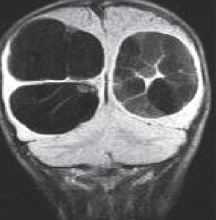

При МРТ головного мозга картина неспецифическая и зависит от содержимого кисты. Если она не содержит жира, то имеет ликворную интенсивность сигнала . В таком случае эпидермоидная киста трудно отличима от арахноидальной, хотя, как правило, не столь однородная. На МРТ типа FLAIR и диффузионно-взвешенных МРТ изображениях содержимое эпидермоидов светлее ликворного. Жировое содержимое, такие эпидермоиды еще называют холестеатомой, приводит к высокому сигналу на Т1-взвешенных МРТ головного мозга. Видимо, он обусловлен липидами, но не холестеролом. На Т2-взвешенных МРТ головного мозга он менее интенсивен чем ликвор. Контуры эпидермоидов всегда четкие. Холестеатомы составляют всего 3-5% от эпидермоидов. В 15-20% случаев встречается кальцификация по переферии кисты. Редко наблюдается контрастирование стенок.

Арахноидальные кисты представляют собой скопление ликвора между листками расщепленной паутинной оболочки. Арахноидальная киста обычно не сопровождается другими мальформациями. Незначительная часть арахноидальных кист имеет приобретенное происхождение - следствие лептоменингита, операции или кровоизлияния. Частота составляет около 1% от внутричерепных образований. Соотношение полов М:Ж, как 4:1. Типичная локализация - средняя черепная ямка (в области Сильвиевой борозды 50%), межполушарная щель, мосто-мозжечковый угол (11%), за скатом или на уровне четверохолмия (10%), в области червя мозжечка (9%), реже в области межножковой и предмостовой цистерн (3%), а также супраселлярной и хиазмальной цистерн. Ретроцеребеллярная арахноидальная киста довольно часто встречаются за мозжечком и отличима от mega cisterna только по неизменённой задней черепной ямке. Содержимое кисты чисто ликворное, стенки гладкие, чётко очерченные, внутри кисты могут быть перегородки. Мелкие арахноидальные кисты очень трудно увидеть. Меняя ширину окна и его уровень на Т1-взвешенных МРТ изображениях можно заметить, что киста чуть светлее ликвора. Дифференциальная диагностика с эпидермальными кистами лучше осуществляется с помощью МРТ последовательности FLAIR. Эпидермальные кисты становятся яркими, в отличие от гипоинтенсивных арахноидальных.